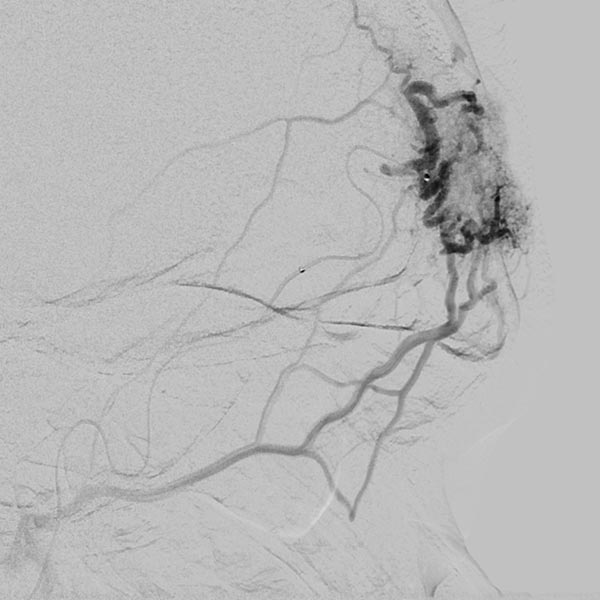

Completion angiography with contrast injection into the right external carotid artery demonstrates complete occlusion of the nidus of the arteriovenous malformation. On account of the subtraction imaging technique, the cast appears white here (subtracted).

To ensure long-term success and avoid recurrence, as well as to improve the cosmetic result (persistent redness of the skin on the forehead), the complete occluded nidus was resected. To date, the patient has had no recurrence.